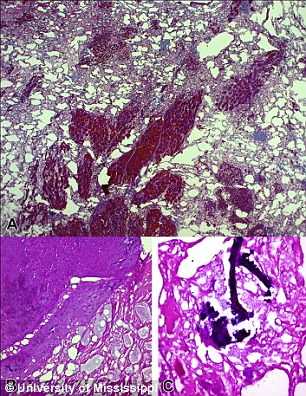

Dr Richard D. deShazo un profesor de medicina la Universitatea din Mississippi a analizat doua varietati de "chicken nugget" (KFC si Chick-Fill-A) la microscop.

Conform descoperirilor facute la primul restaurant, doar 50% din continutul produselor era carne, restul fiind doar grasime, vase de sange, nervi si alte tesuturi din diferite parti ale pasarilor care in mod normal nu ar putea fi consumate.

In cel de-al doilea restaurant datele au fost si mai socante: 40% carne si restul era un amestec de grasime, organe si oase de pui. Doctorul a comparat produsele servite in fast-food-uri cu "bucati de resturi de pasare combinate cu "mazga" de grasime si prajite in mult ulei".